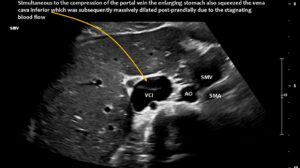

The longitudinal section showing the continuation of the superior mesenteric artery (SMA) into the root of the portal vein reveals an abrupt narrowing of the portal vein, caused by compression from the common hepatic artery.

Enlargement of the superior mesenteric vein can be observed as early as five minutes after eating, progressing to fivefold enlargement of the transsectional area after seven minutes.

Compression of the superior mesenteric vein and its distension not only compresses the duodenum, but also reduces venous return from the small bowel, which can impair food absorption. Blocked blood flow at the compression site can be demonstrated by a whirling blood stream in front of the compression. Subsequent layers demonstrate antegrade and retrograde flow, as can be seen in the layering of blue and red flow inside the enlarged vein, pointing to changing flow directions and the different flow directions in these layers as highlighted by the spectral analyses at the bottom of the image.

Postprandial compression of the vena cava contributed to eating difficulties due to pain caused by obstructed venous return from the abdomen to the heart.